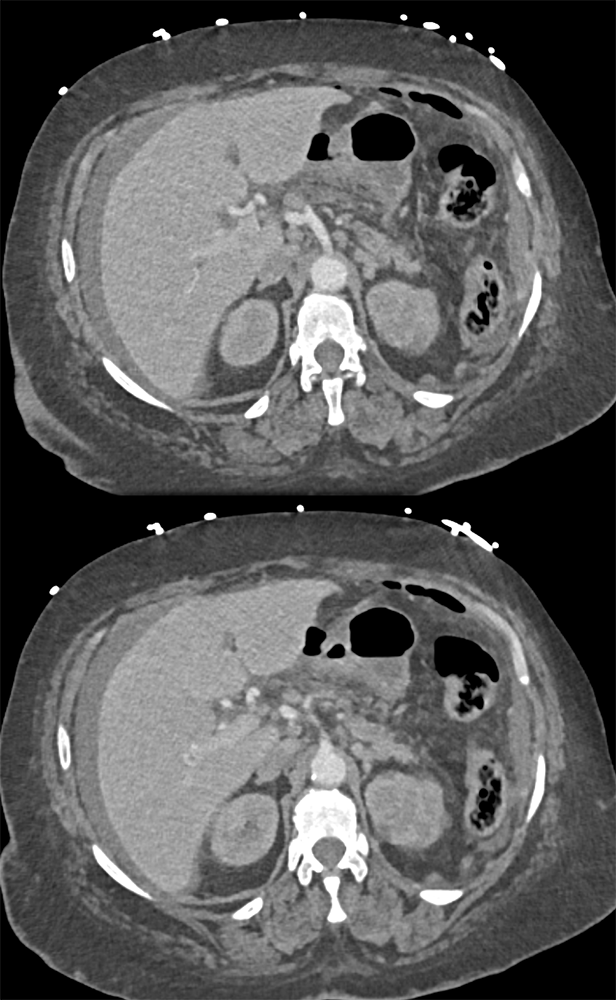

“In our patient, the findings of prominent mucosal folds extending from the pylonic channel on upper gastrointestinal series and the thickened antral wall on CT scans correlate well with the known pathologic appearance of gastnic antral vascular ectasia. Histologically, antral thickening results from a combination of foveolar and fibromuscular hyperplasia. Grossly, the antral fold prominence appears to result from bunching of the mucosa in the thickened, hypercontractile antrum.” Gastric antral vascular ectasia ("watermelon stomach"): radiologic findings. Urban BA, Jones B, Fishman EK, Kern SE, Ravich WJ. Radiology. 1991 Feb;178(2):517-8. |

“Gastric antral vascular ectasia primanily affects women (9:1 female-to-male ratio) aged 56-76 years, and is associated with liver cirrhosis (37%) and achlorhydnia (35%). The usual symptoms are iron-deficiency anemia and melena due to chronic gastrointestinal bleeding from the dilated, superficial, and easily traumatized vessels. Antrectomy is curative, but endoscopic treatment with heat probes or lasers has shown promise.” Gastric antral vascular ectasia ("watermelon stomach"): radiologic findings. Urban BA, Jones B, Fishman EK, Kern SE, Ravich WJ. Radiology. 1991 Feb;178(2):517-8. |